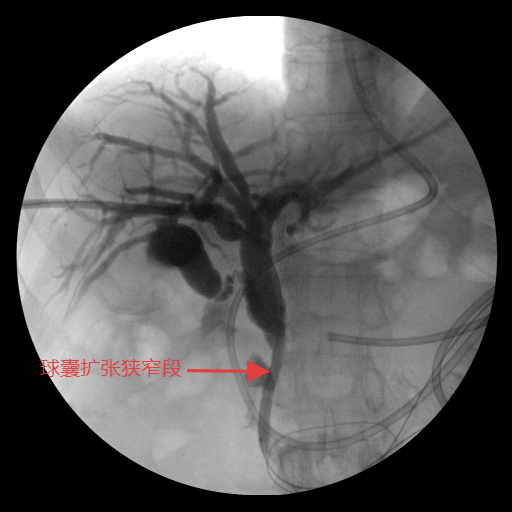

手术在C型臂透视精准引导下开展:团队沿原PTCD通道送入“头发丝”细的导丝,首次穿刺即成功,精准选取最优胆道入路以规避组织损伤;导丝跨越梗阻段时,团队密切协作避免反复抽拉引发肠道逆行感染。针对外压性病灶导致的狭窄,先以球囊扩张狭窄部位,再将装载I-125的自膨式可载粒子胆道支架精准送入胆总管梗阻段并缓慢释放。术后造影显示,支架扩张效果良好,造影剂可通畅流入十二指肠,患者生命体征平稳。

球囊扩张